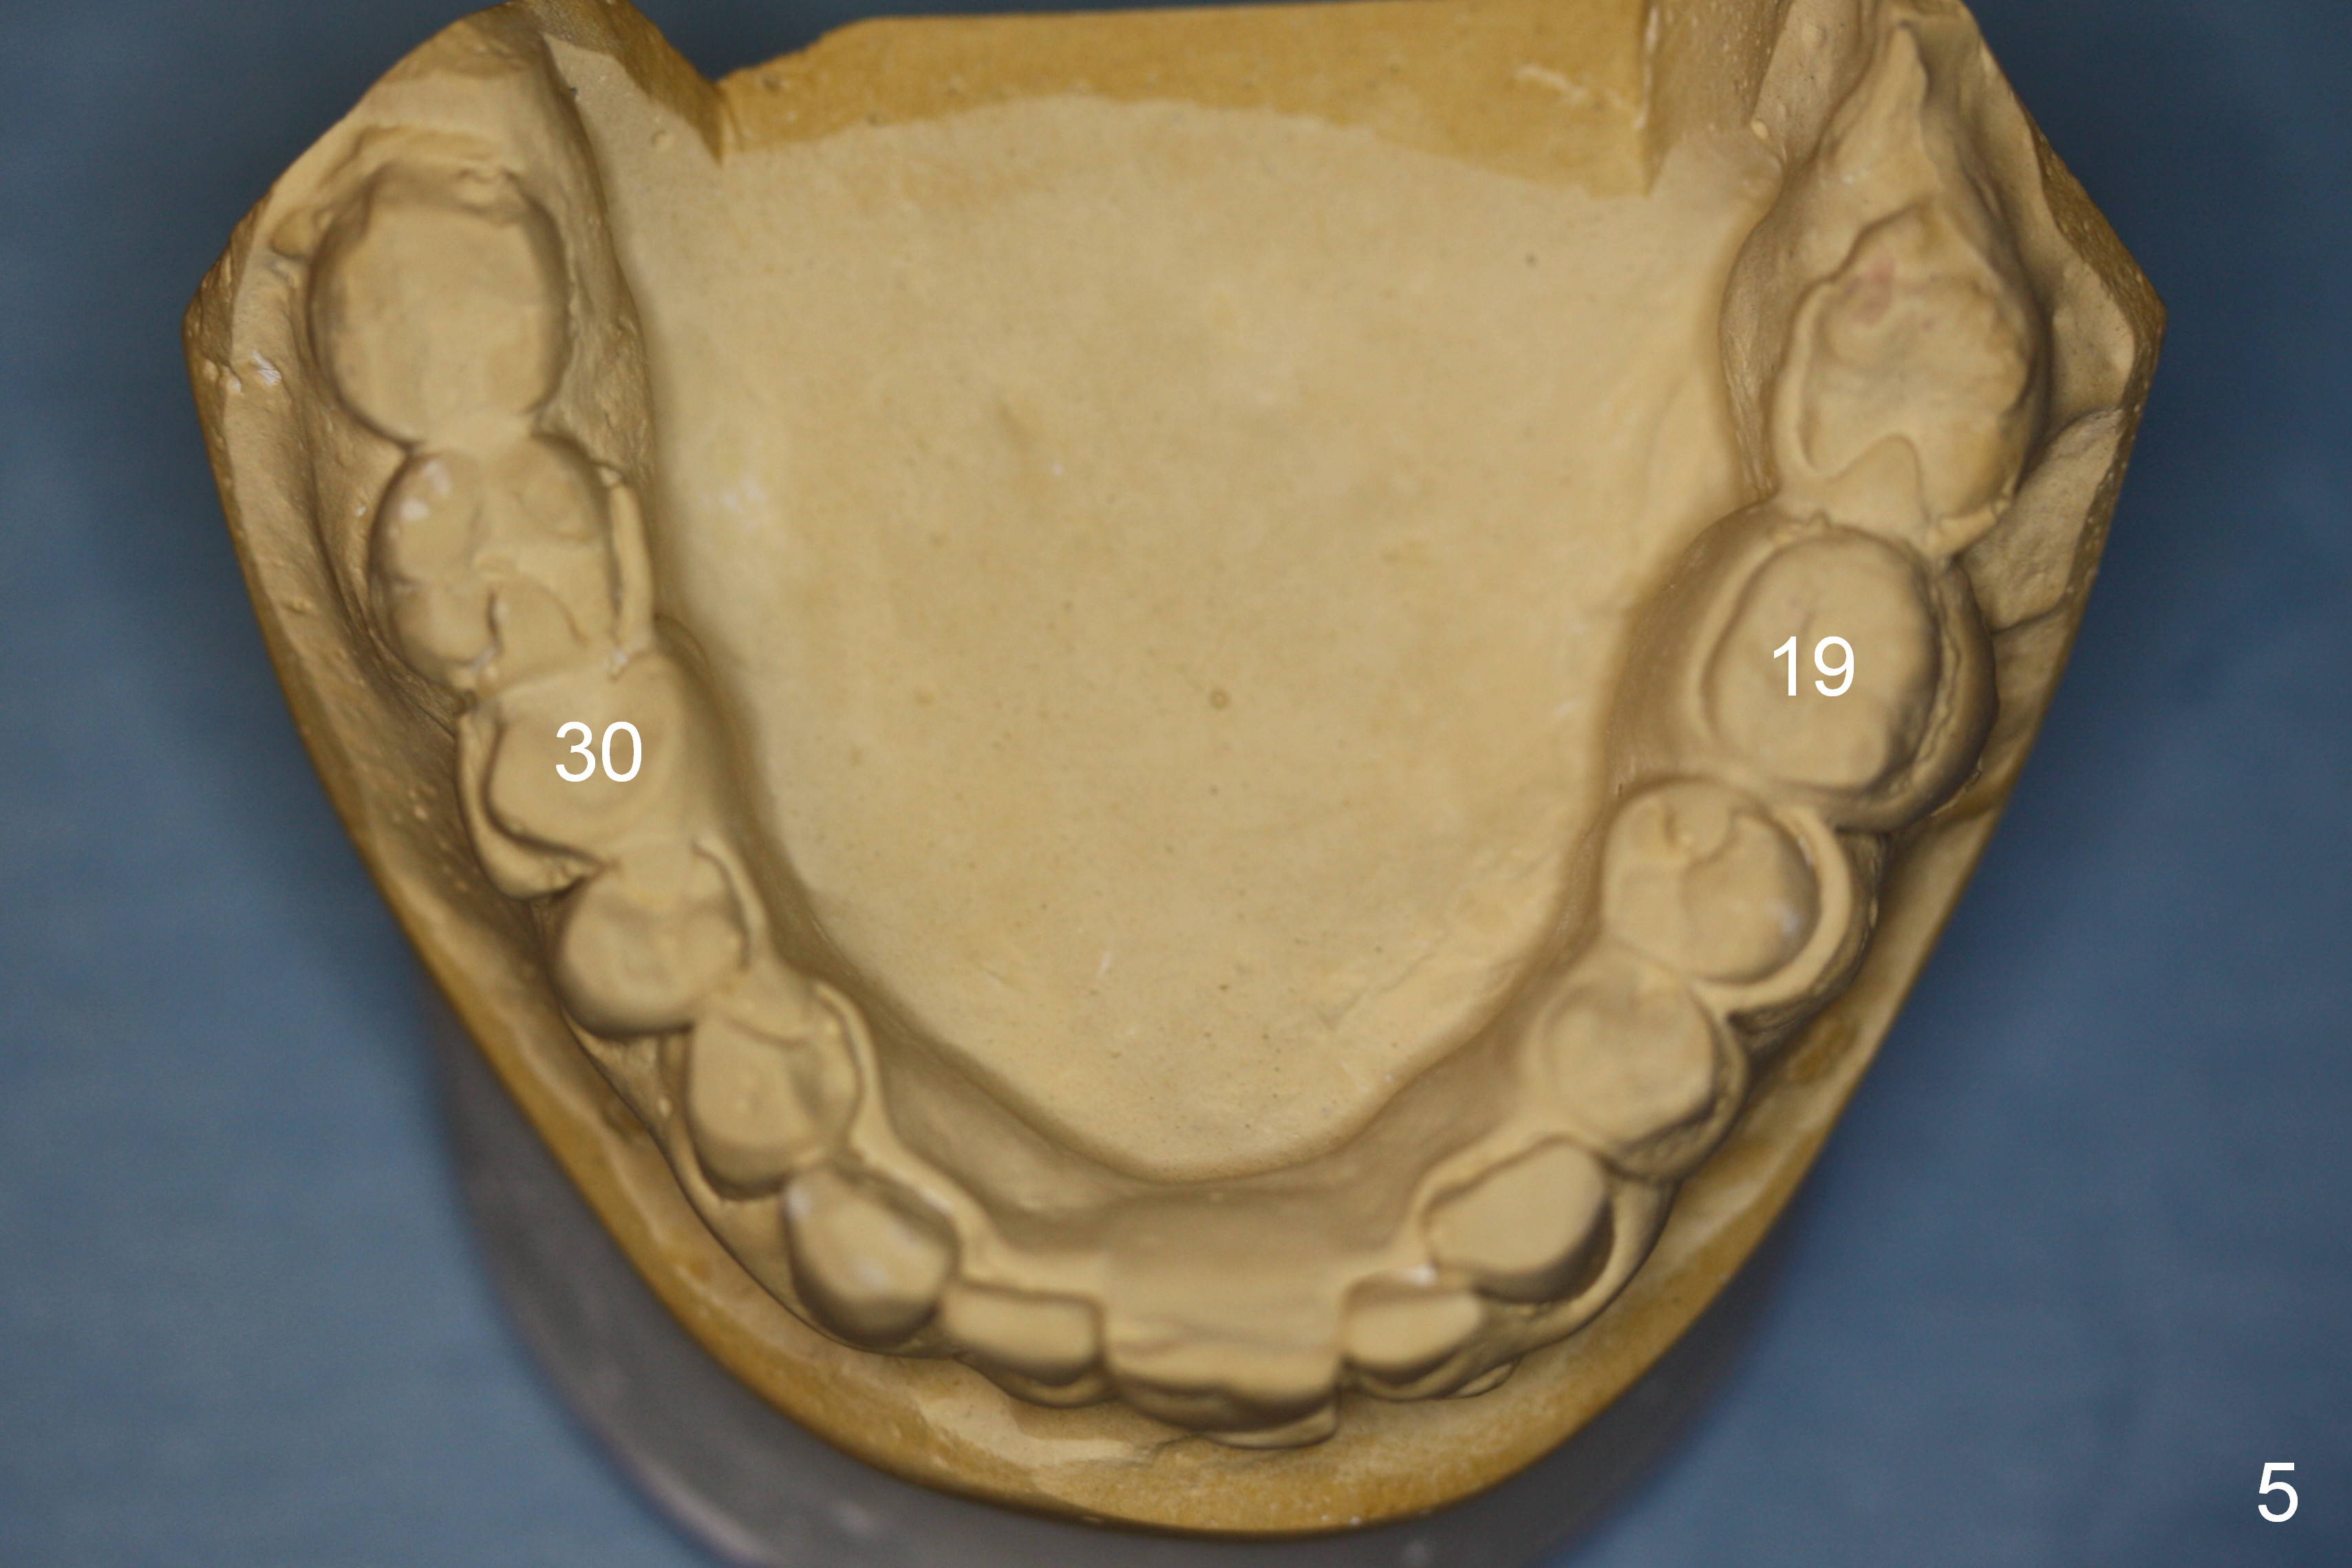

A 52-year-old man has multiple missing teeth. Since he has a lower partial denture (Fig.5), implants will be placed at the sites of #14 and 15 first (Fig.1). The site of #14 may need bone expansion if bone density is low, whereas the ridge at #15 is wide (Fig.2). There is no problem in height at the sites of #14 and 15 (Fig.3).

The buccolingual width at the sites of #19 and 21 appears narrow (Fig.4). On the other hand, the mesiodistal width at #19 seems to be wider than one molar and narrower than two (Fig.4-6). If CBCT and/or surgery confirms that the buccolingual bony width is narrow, two small diameter implants will be placed with restoration of two bicuspids.